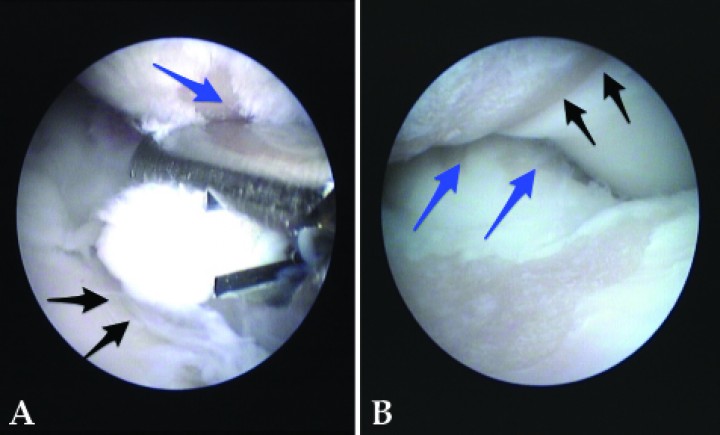

El uso de la artroscopia para el diagnóstico y tratamiento de la DC, especialmente en los casos de EPCM y OCD (Figs. 2A-2D) ha supuesto un avance con respecto a los métodos tradicionales, ya que el examen de la articulación es más completo y minucioso que con la artrotomía,[ Bouck GR. A comparison of surgical and medical treatment of fragmented coronoid process and osteochondritis dissecans of the canine elbow. Vet Comp Orth Traum, 1995, 177. , Burton NJ, Owen MR, Kirk LS, et al. Conservative versus arthroscopic management for medial coronoid process disease in dogs: A prospective gait evaluation. Vet Surg 2011; 40: 972-980. [PubMed] , Meyer-Lindenberg A, Langhann A, Fehr M, et al. Arthrotomy versus arthroscopy in the treatment of the fragmented medial coronoid process of the ulna (FCP) in 421 dogs. Vet Comp Orthop Traumatol 2003; 16: 204-210. ] incluso del compartimento lateral (Fig. 3A), muy difícil de evaluar con cirugía abierta, permitiendo de una forma mínimamente invasiva la extracción de fragmentos osteocondrales y el legrado de las lesiones resultantes (Fig. 3B) con mínimas complicaciones.[ Perry K, Li L. A retrospective study of the short- term complication rate following 750 elective elbow arthroscopies. Vet Comp Orthop Traumatol 2014; 27: 68-73. [PubMed] , Ridge PA. A retrospective study of the rate of post- operative septic arthritis following 353 elective arthroscopies. J Small Anim Pract 2011; 52: 200-202. [PubMed] ]

<p>(<strong>A</strong>) Imagen de artroscopia de un Pastor del Cáucaso de 6 meses de edad mostrando un fragmento de cartílago semidesprendido (flecha) en un caso de OCD de cóndilo humeral. (<strong>B</strong>) Imagen de artroscopia de un Golden Retriever de 9 meses. Se detecta una fisura (flechas) en el ápex del proceso coronoides medial que podría haber pasado desapercibida durante una artrotomía. (<strong>C</strong>) Imagen del mismo animal de la Figura 2B. Aspecto del ápex del proceso coronoides una vez desencajado completamente de su lecho con un palpador. Se puede apreciar el grosor del hueso subcondral. Posteriormente, se procedió a su extracción y al legrado de la zona. (<strong>D</strong>) Imagen de artroscopia en un caso de PCF y OCD simultáneos. Movilización del proceso coronoides fragmentado con un palpador (flecha negra). La parte medial del cóndilo humeral muestra una lesión de OCD (flecha roja), con el fragmento de cartílago todavía <em>in situ</em>.</p>

Figura 2

(A) Imagen de artroscopia de un Pastor del Cáucaso de 6 meses de edad mostrando un fragmento de cartílago semidesprendido (flecha) en un caso de OCD de cóndilo humeral. (B) Imagen de artroscopia de un Golden Retriever de 9 meses. Se detecta una fisura (flechas) en el ápex del proceso coronoides medial que podría haber pasado desapercibida durante una artrotomía. (C) Imagen del mismo animal de la Figura 2B. Aspecto del ápex del proceso coronoides una vez desencajado completamente de su lecho con un palpador. Se puede apreciar el grosor del hueso subcondral. Posteriormente, se procedió a su extracción y al legrado de la zona. (D) Imagen de artroscopia en un caso de PCF y OCD simultáneos. Movilización del proceso coronoides fragmentado con un palpador (flecha negra). La parte medial del cóndilo humeral muestra una lesión de OCD (flecha roja), con el fragmento de cartílago todavía in situ.